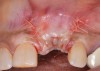

It is important to point out that not all implants presenting with mucogingival or esthetic complications require explantation, especially when the affected implants are partially supporting a multiple-unit restoration. This can be demonstrated in the following case. Implants were placed almost 20 years prior to the patient presenting with advanced soft-tissue recession on the maxillary right arch (Figure 15). There was a lack of keratinized/attached mucosa and buccal bone deficiency. This bone deficiency was not pathologic, but the result of physiologic remodeling,6 which was evident following flap reflection (Figure 16). At the time that these implants were placed, simultaneous bone augmentation to offset the diminution of the arch after tooth extractions was not a prerequisite.7 Also, the importance of soft-tissue augmentation at the time of immediate implant placement was not fully appreciated when this patient was originally treated.8,9 Formation of biologic width combined with a thin periodontal biotype often results in significant crestal bone loss.10 More recently, the importance of increasing soft-tissue thickness as it relates to more favorable crestal bone preservation has been demonstrated by Linkevicius and colleagues.11 Removing these implants would commit the patient to remaking her large prosthesis; therefore, she was interested in maintaining them with a corrective mucogingival procedure.

After gentle debridement with glycine air abrasion and sterile saline, a cross-linked, porcine collagen bone matrix (OSSIX® VOLUMAX; Datum Dental Ltd.) was placed over the buccal aspect of all three affected implants (Figure 17). Next, a subepithelial, connective tissue graft harvested from the right aspect of the patient's hard palate was affixed over the bone scaffold and exposed implants and abutments (Figure 18). And finally, a coronally advanced flap was sutured over the hard- and soft-tissue grafts. The 1-month, follow-up photograph demonstrates incomplete, but significant coverage of the previously exposed implants and abutments (Figure 19).

(15.) Due to physiologic remodeling of the alveolar ridge, facially inclined implant positions, and ineffective augmentation at time of placement, these three implants are experiencing mucosal recession.

Figure 15

(16.) Following flap reflection, the buccal bone deficiencies are evident.

Figure 16

(17.) A cross-linked collagen bone graft scaffold is applied over the debrided implant surfaces to help reconstruct a portion of the deficient buccal bone.

Figure 17

(18.) A subepithelial, connective tissue graft from the palate is affixed over the collagen bone scaffold and around the abutments of the three involved implants.

Figure 18